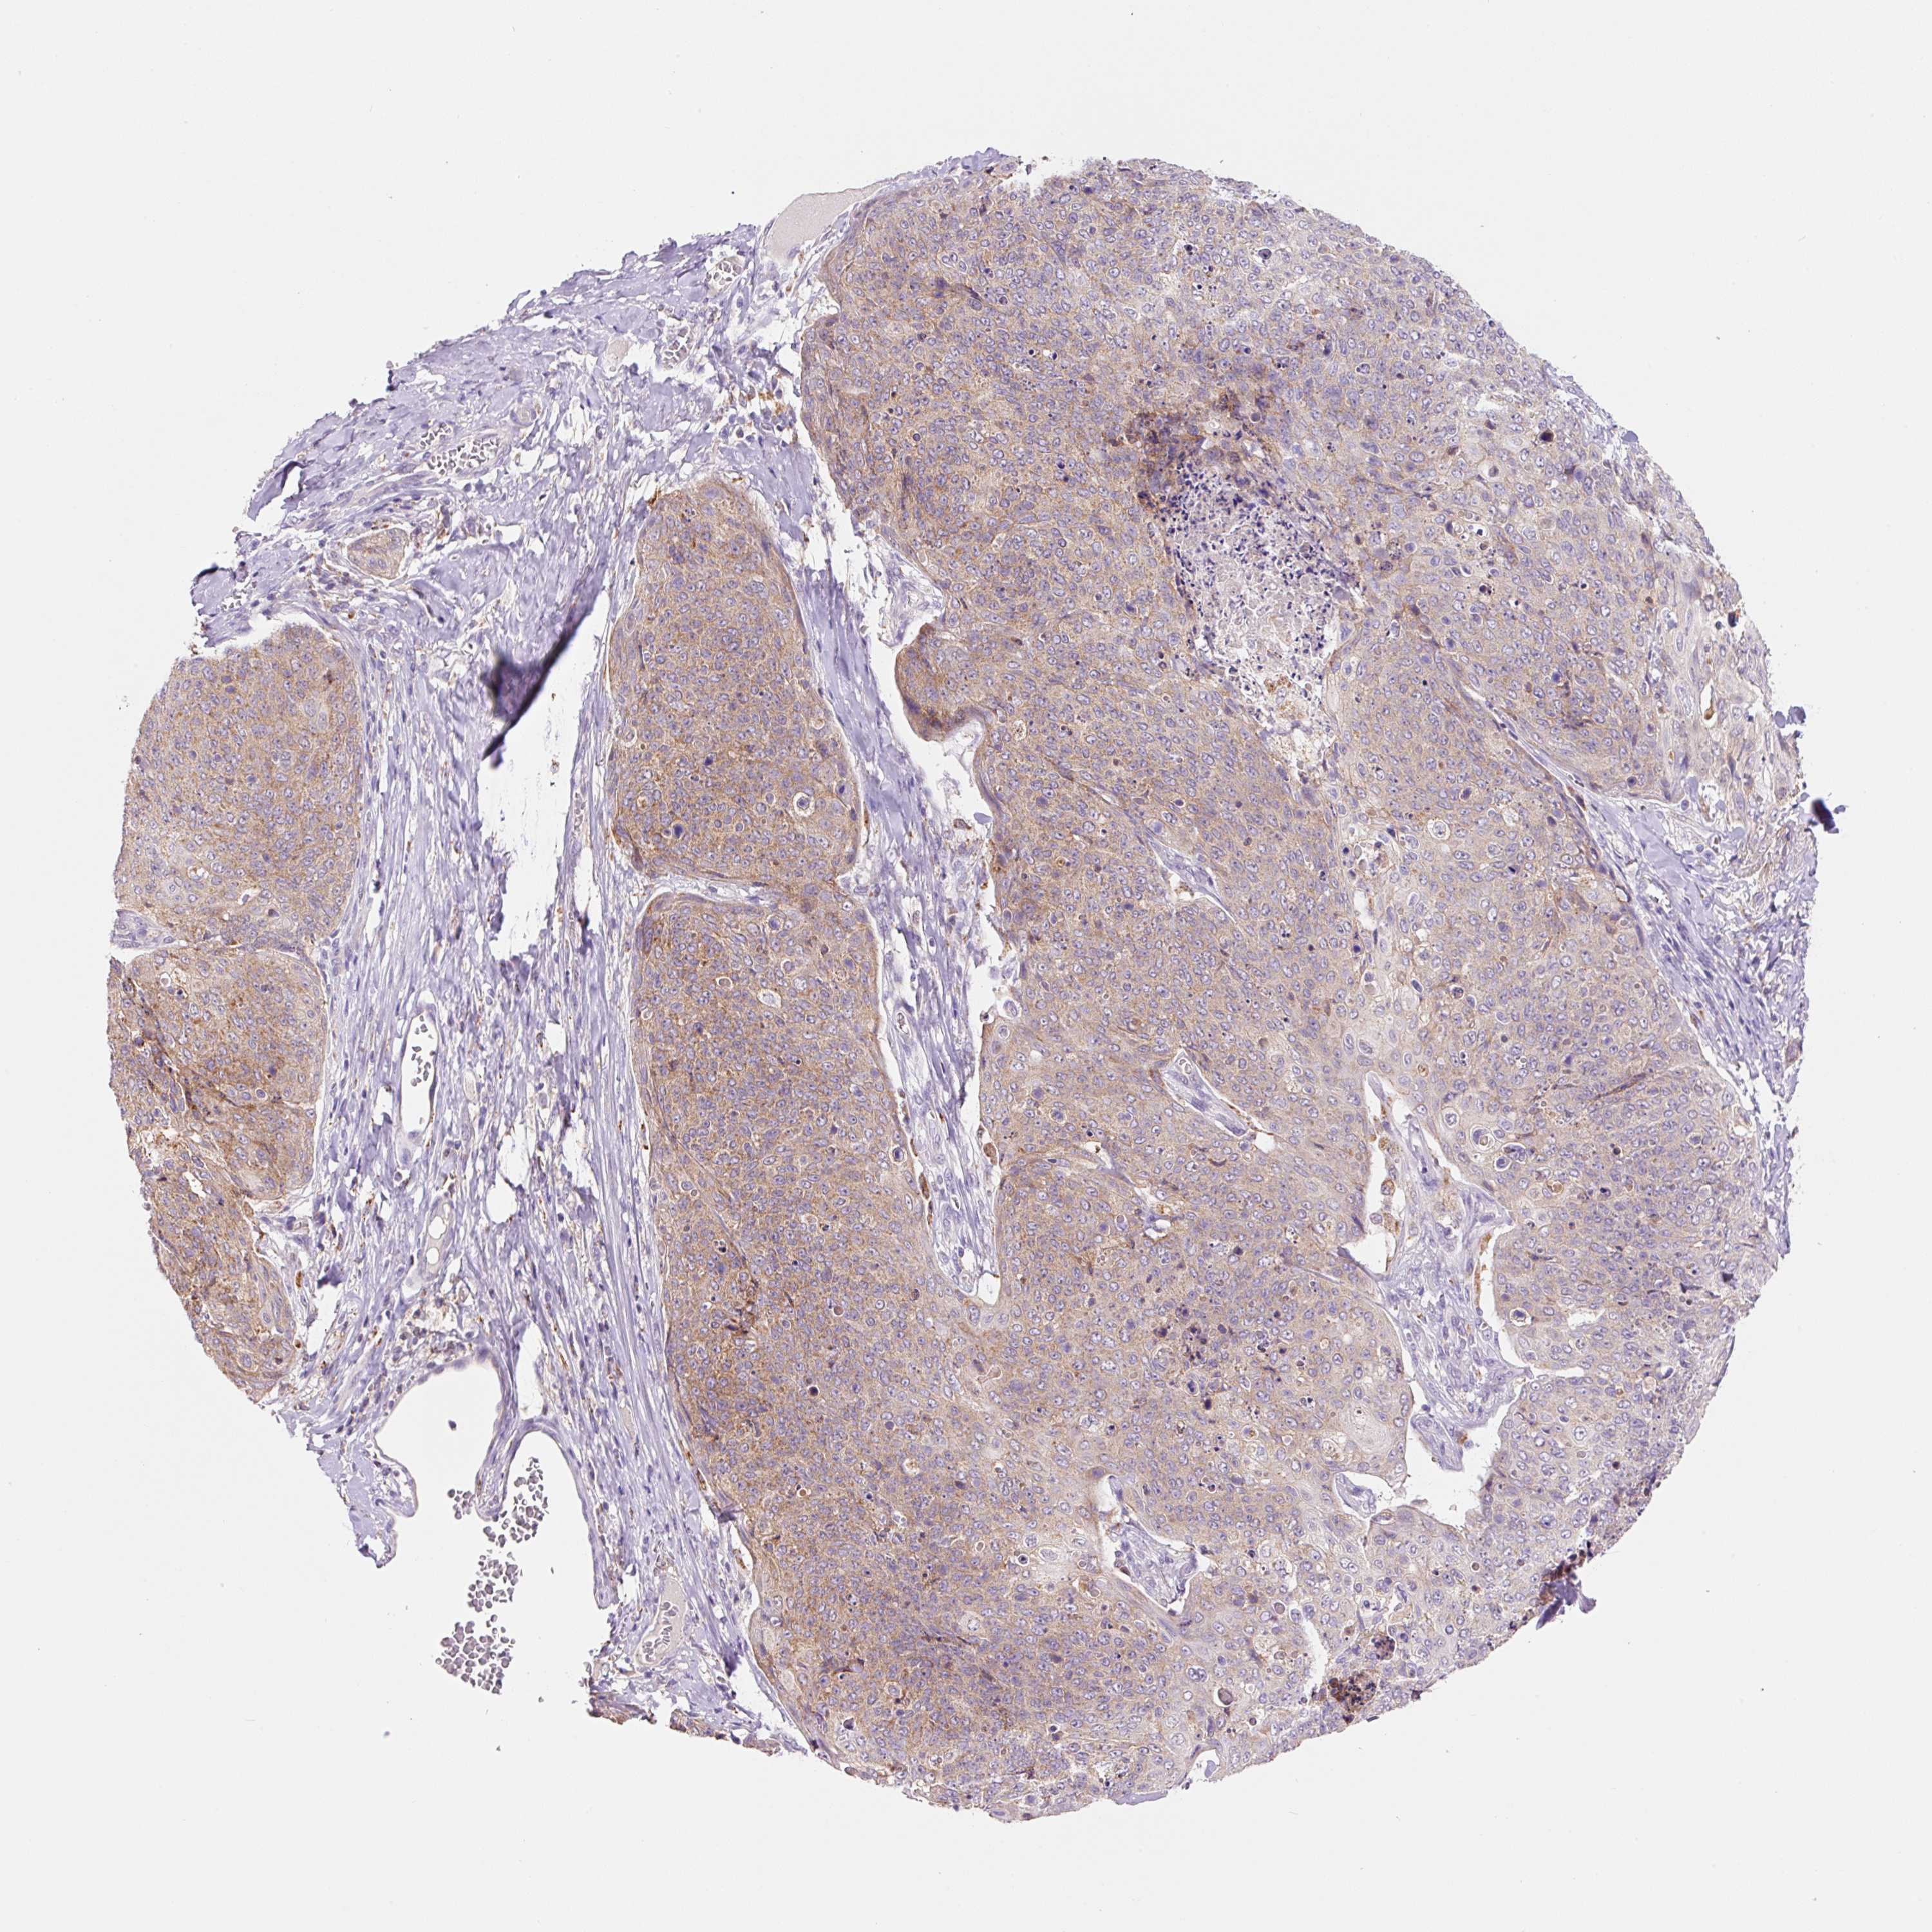

SKIN CANCER - Protein expressioni

A mouse-over function shows sample information and annotation data. Click on an image to view it in a full screen mode. Samples can be filtered based on level of antibody staining by selecting one or several of the following categories: high, medium, low and not detected. The assay and annotation is described here.

Antibody stainingi

Antibody staining in the annotated cell types in the current human tissue is reported as not detected, low, medium, or high, based on conventional immunohistochemistry profiling in selected tissues. This score is based on the combination of the staining intensity and fraction of stained cells.

Each image is clickable and will lead to virtual microscopy that enables deeper exploration of all samples and also displays staining intensity scores, fraction scores and subcellular localization as well as patient and tissue information for each sample.

Antibody HPA051162

Basal cell carcinoma

Squamous cell carcinoma, NOS

Squamous cell carcinoma, metastatic, NOS

Squamous cell carcinoma in situ, NOS